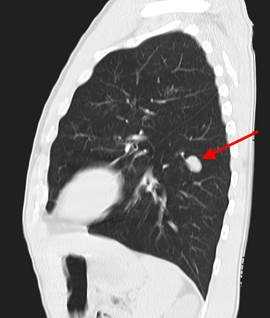

КТ органов грудной клетки. Очаговое объемное образование верхней доли (S3) левого легкого с включениями кальция (верифицированная туберкулома)

Основой для верификации диагноза остается рентгенография легких. Характерный рентгенологический признак - наличие ограниченного затемнения правильной округлой формы, с четкими контурами и преимущественно однородной структурой. В стадии обострения контуры туберкуломы легкого становятся размытыми за счет появления перифокальной инфильтрации.